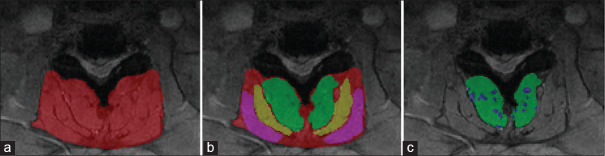

Materials and methods: A retrospective review was conducted on cervical myelopathy patients treated with laminoplasty between January 2019 and January 2022 at a tertiary care center. Inclusion criteria included pre- and 1-year postoperative X-rays and magnetic resonance imaging within 6 months presurgery. PKD was defined as loss of cervical lordosis greater than -10° based on the C2-7 Cobb angle. Fatty infiltration was evaluated using Goutallier classification and voxel quantification.

Results: Among 44 patients, 4 developed PKD. Qualitatively, 32 patients were classified as Goutallier 0-1.5, 6 were Goutallier 1.5-2.5, and 6 Goutallier 2.5-4. There is a significant association between the Goutallier grade and PKD occurrence after 1 year (P = 0.00085). Quantitatively, the average fatty infiltration percentage for the kyphotic patients was 23.3% ± 5.81% versus 13.8% ± 9.83% for nonkyphotic patients. A significant association was found between the percentage of fatty infiltration and the PKD after 1 year (P = 0.045). The optimal fat cutoff between kyphotic and nonkyphotic patients was 23% (P = 0.056).